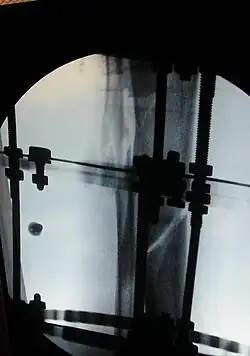

The photographs and radiographs illustrate the application and emplacement of an external fixator, an Ilizarov apparatus, to repair the open fracture of the lower left leg of a man. The photographs were taken four weeks after the patient fractured the shinbone (tibia) and the calfbone (fibula) of his left leg, and two weeks after the surgical emplacement of the Ilizarov apparatus to immobilise the leg and isolate the wound and fracture site to facilitate healing.

X-ray of the open fracture of the left leg; the external fixator was installed ca. 24 hrs. in hospital.